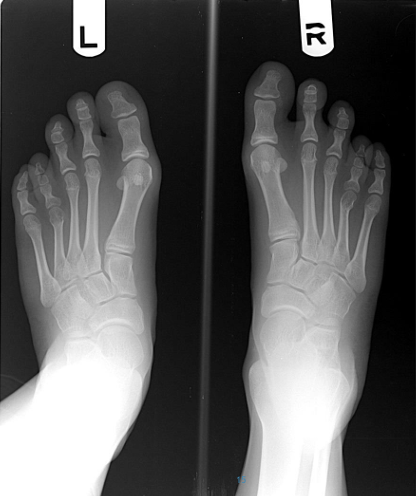

À quoi ressemble un 4 métatarse plus court?

A